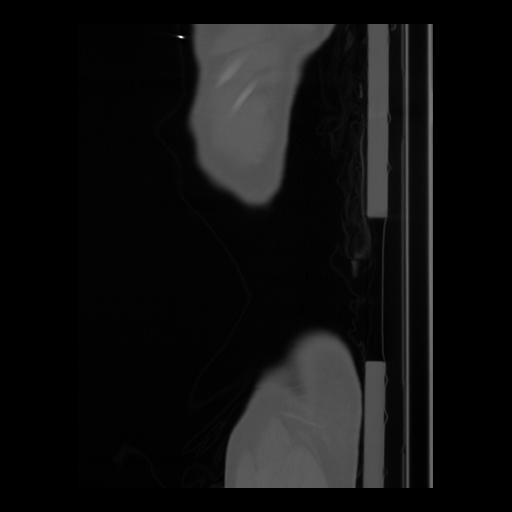

36 CUERPO,CE,Sagittal,3.000,CUERPO,Sagittal,